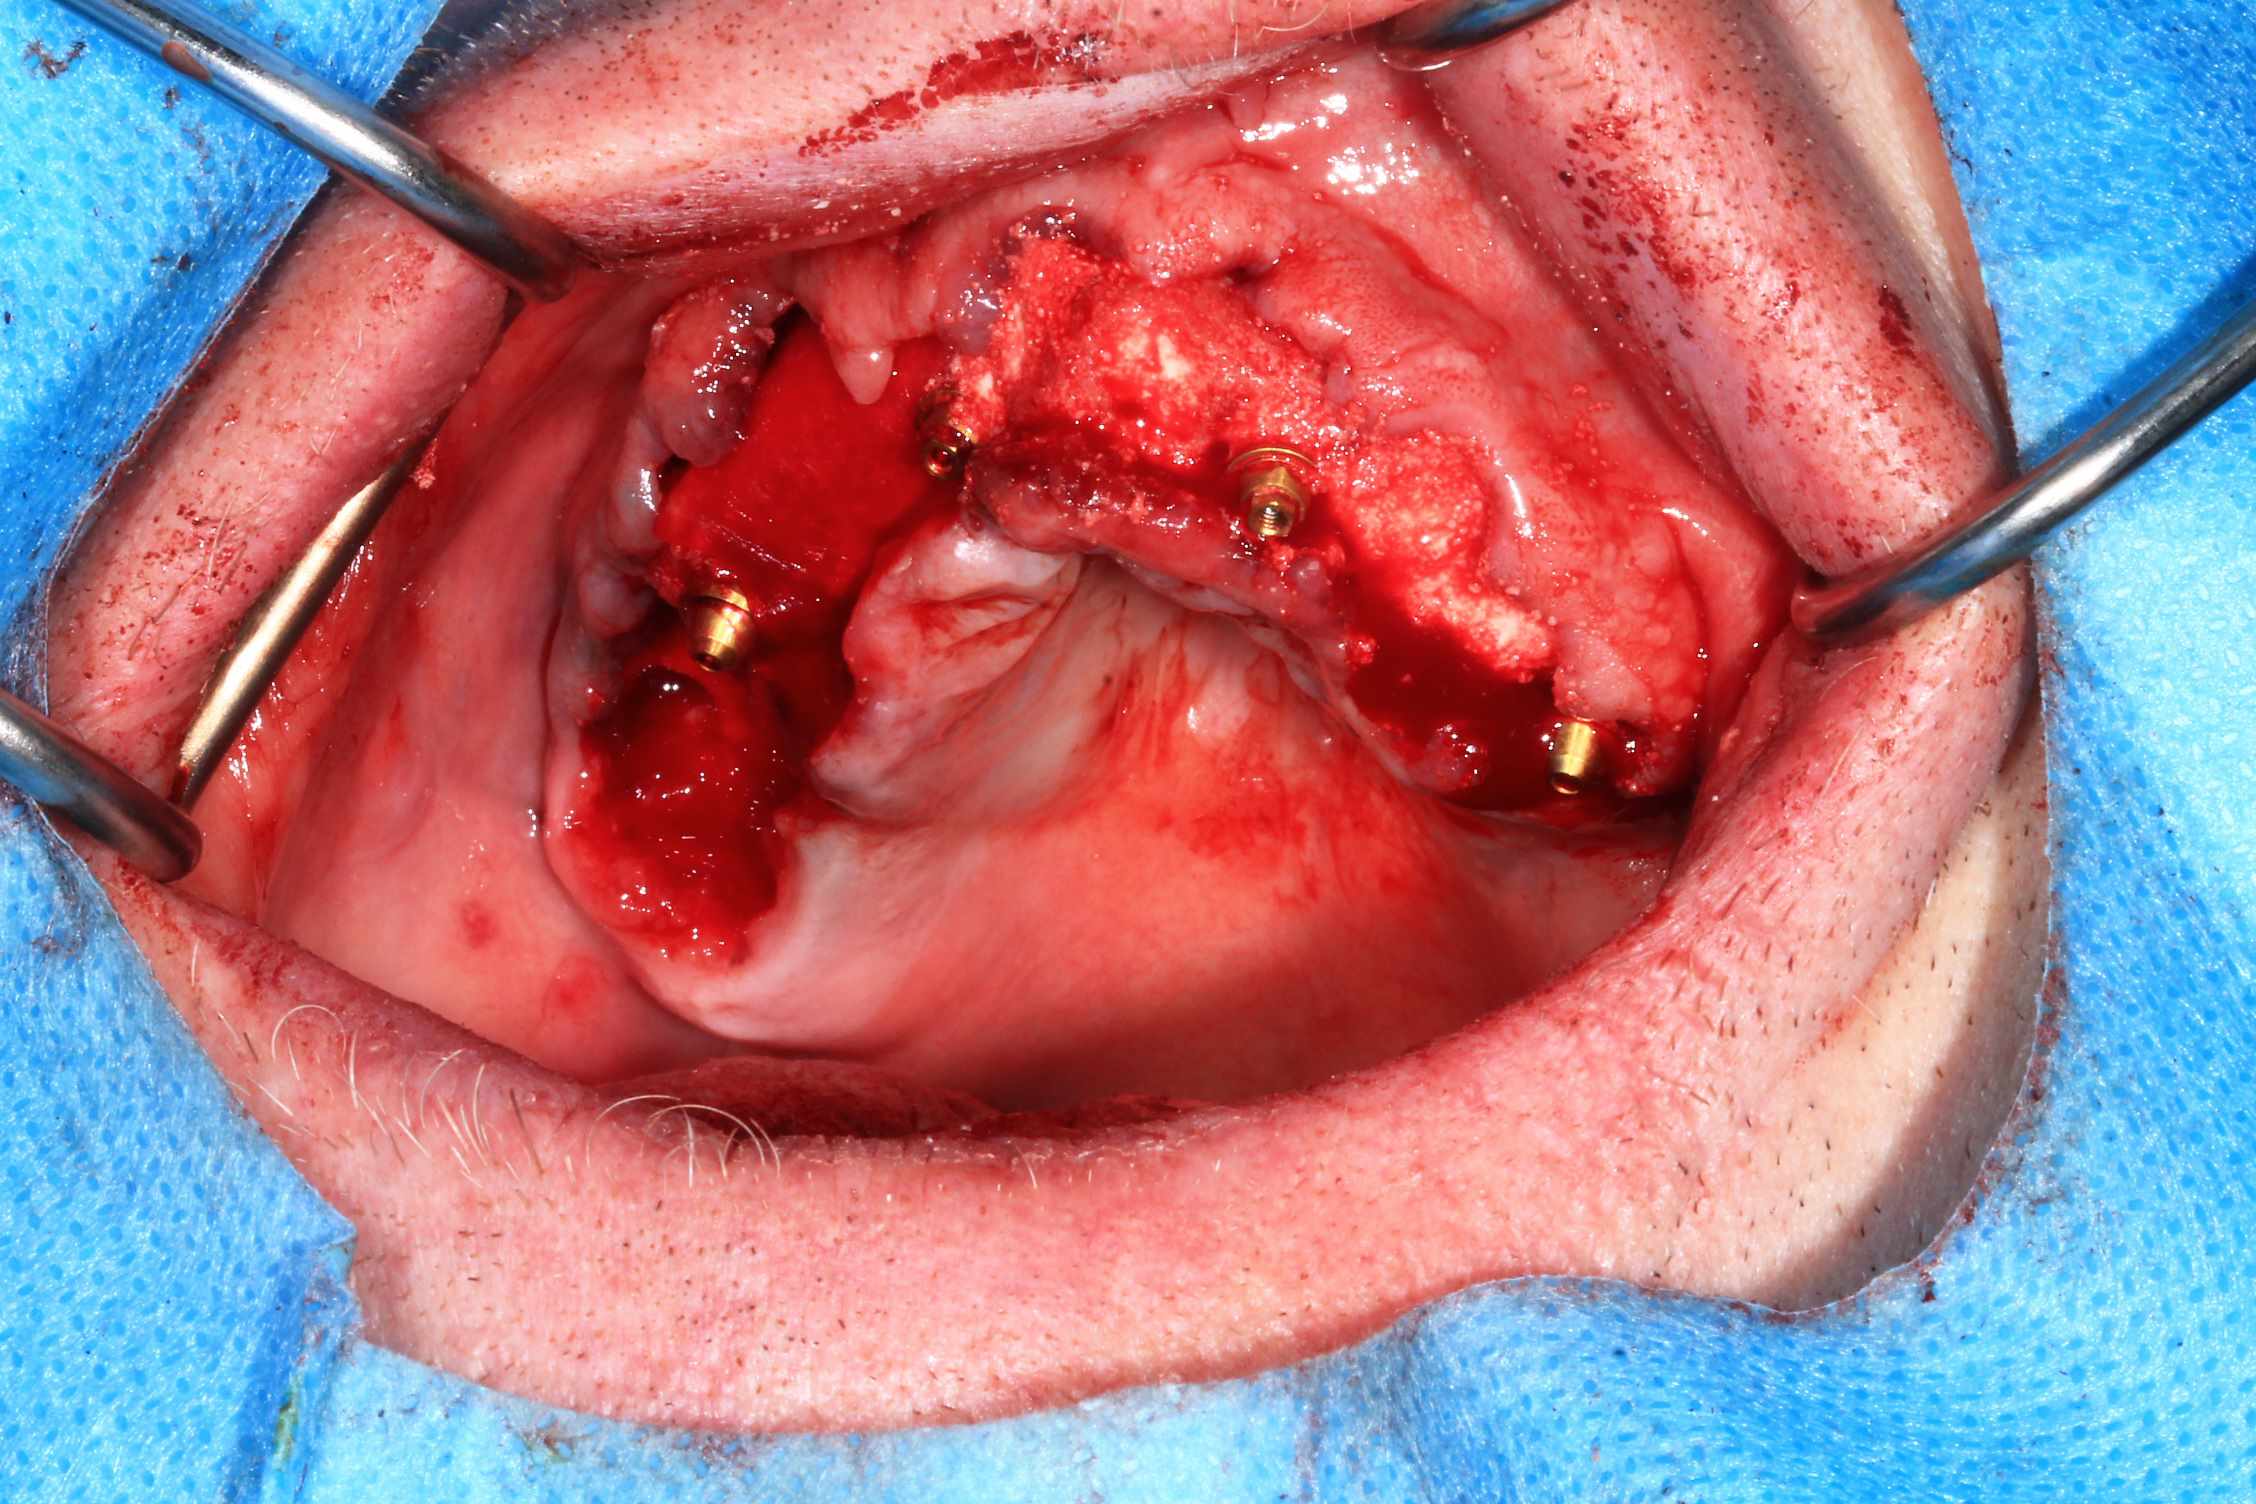

Mais celui la est tout chaud ( de vendredi dernier ) et j'ai regarder le temps que j'ai mis ( beaucoup plus complexe, donc plus long ). on va l'appeller Cas 2.

3 h de planif, modélisation du guide, puis 2 h environ pour la simulation de la chir , le modelisation et l'impression du bridge, qui tombe pile, zero retouche occlusale.

Avec un plan de traitement qui est suceptible de débat :)

Cas 2 , suite : avec une saussage au passage..

le patient arrive a 9 h, Prise de sang, PRF, injection de corticoïde, anesthésie et installation au bloc. Premier coup de bistouri a 9h30. Dernière suture a 11h30.